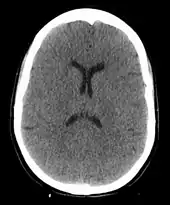

The cause of death in hanging depends on the conditions related to the event. When the body is released from a relatively high position, the major cause of death is severe trauma to the upper cervical spine. The injuries produced are highly variable. One study showed that only a small minority of a series of judicial hangings produced fractures to the cervical spine (6 out of 34 cases studied), with half of these fractures (3 out of 34) being the classic "hangman's fracture" (bilateral fractures of the pars interarticularis of the C2 vertebra).[26] The location of the knot of the hanging rope is a major factor in determining the mechanics of cervical spine injury, with a submental knot (hangman's knot under the chin) being the only location capable of producing the sudden, straightforward hyperextension injury that causes the classic "hangman's fracture".

The side, or subaural knot, has been shown to produce other, more complex injuries, with one thoroughly studied case producing only ligamentous injuries to the cervical spine and bilateral vertebral artery disruptions, but no major vertebral fractures or crush injuries to the spinal cord.[27] Death from a "hangman's fracture" occurs mainly when the applied force is severe enough to also cause a severe subluxation of the C2 and C3 vertebra that crushes the spinal cord and/or disrupts the vertebral arteries. Hangman's fractures from other hyperextension injuries (the most common being unrestrained motor vehicle accidents and falls or diving injuries where the face or chin suddenly strike an immovable object) are frequently survivable if the applied force does not cause a severe subluxation of C2 on C3.

In the absence of fracture and dislocation, occlusion of blood vessels becomes the major cause of death, rather than asphyxiation. Obstruction of venous drainage of the brain via occlusion of the internal jugular veins leads to cerebral oedema and then cerebral ischemia. The face will typically become engorged and cyanotic (turned blue through lack of oxygen). Compromise of the cerebral blood flow may occur by obstruction of the carotid arteries, even though their obstruction requires far more force than the obstruction of jugular veins, since they are seated deeper and they contain blood in much higher pressure compared to the jugular veins.[28]

When cerebral circulation is severely compromised by any mechanism, arterial or venous, death occurs over four or more minutes from cerebral hypoxia, although the heart may continue to beat for some period after the brain can no longer be resuscitated. The time of death in such cases is a matter of convention. In judicial hangings, death is pronounced at cardiac arrest, which may occur at times from several minutes up to 15 minutes or longer after hanging.